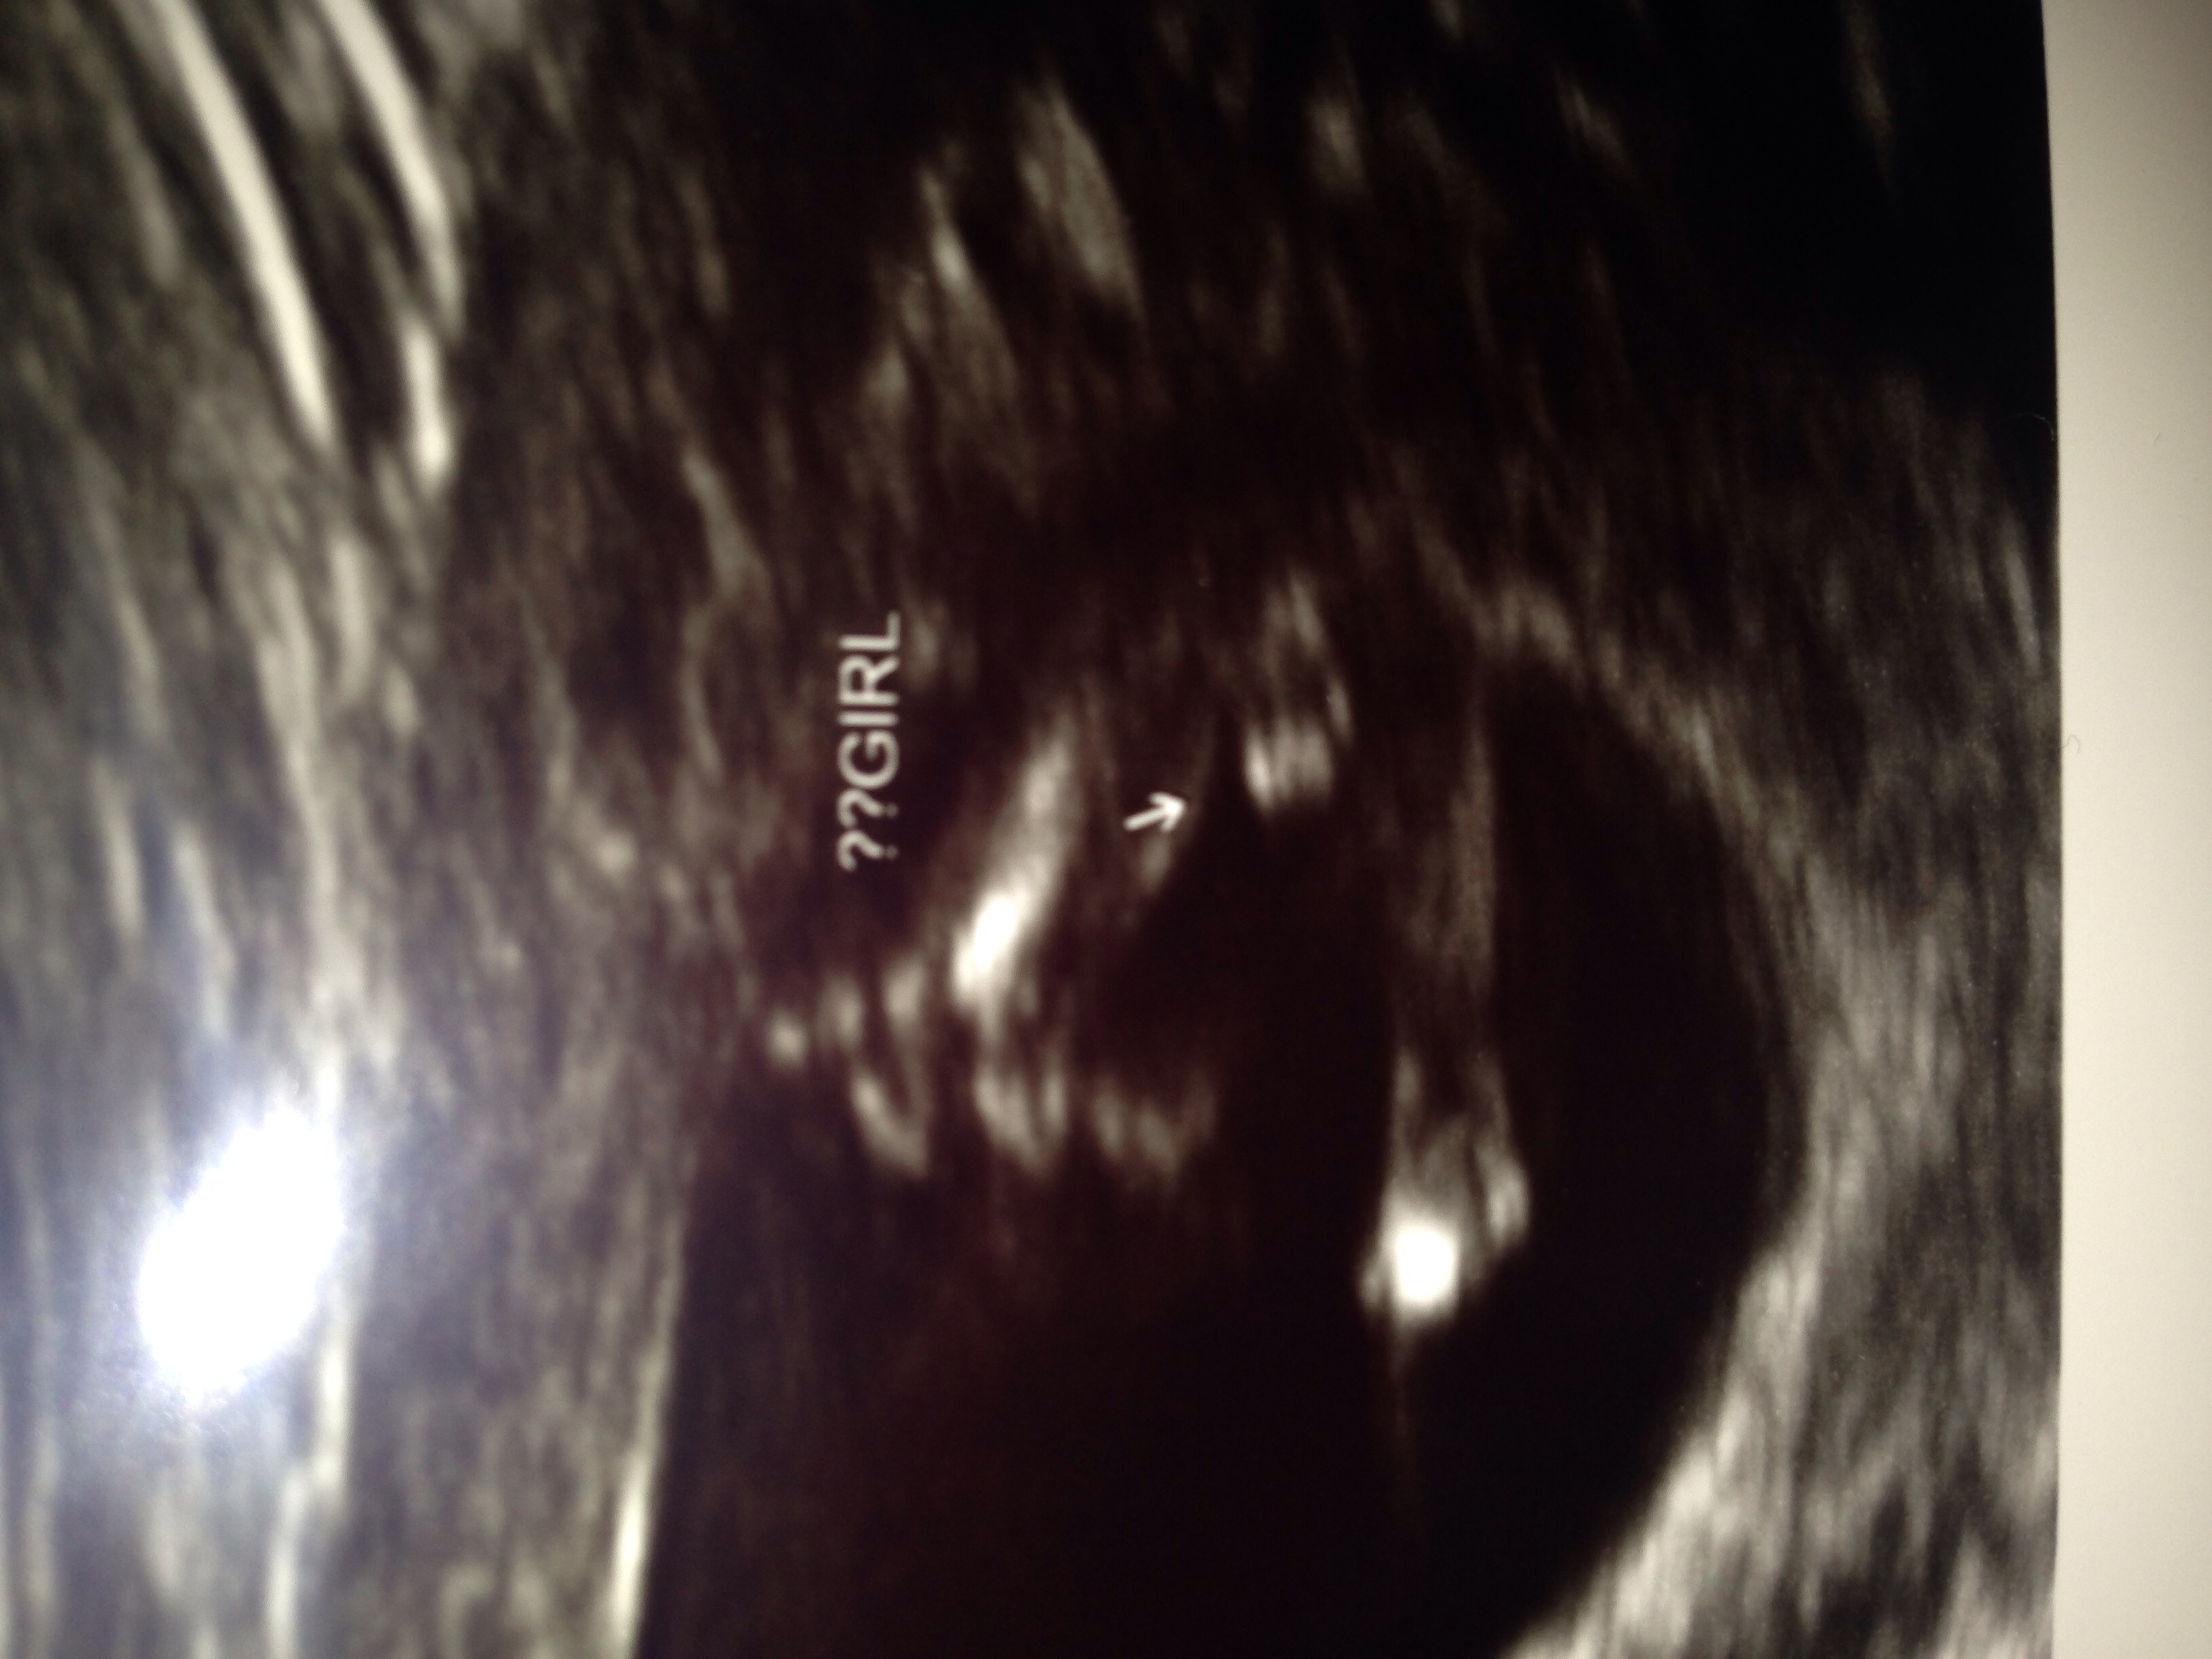

Attachment 17500We had our nt scan yesterday, going by LMP I am 12 weeks 1 day, but baby was measuring ahead at 13weeks 2 days. I got a nub and a potty shot. The tech says she's 80% sure it's a girl. Thoughts and second opinions would be amazing. Thank you very much :) Attachment 17499